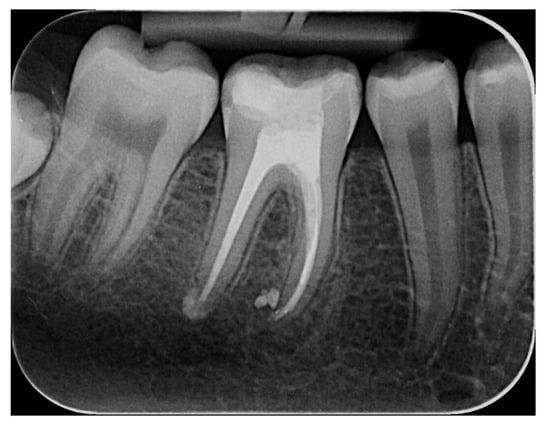

The Combination of Diode Laser and Ozonated Water in the Treatment of Complicated Pulp Gangrene

2.1. Study Participant

2.2.1. Chemomechanical Debridement of Endodontic Space and Root Canal Filling